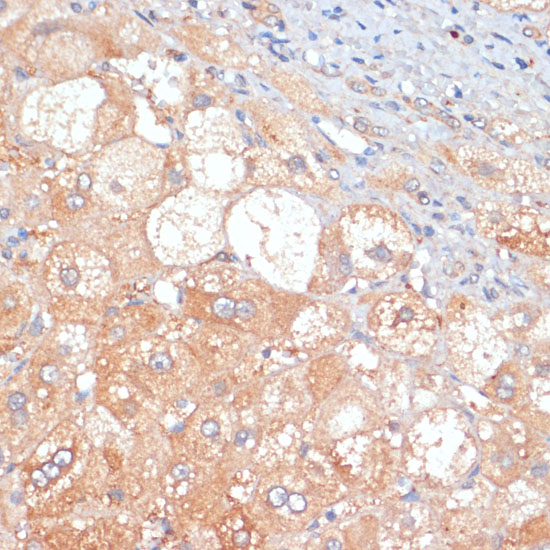

Immunohistochemistry of paraffin-embedded human liver cancer using RIP3 antibody at dilution of 1:100 (40x lens).

Immunohistochemistry of paraffin-embedded mouse pancreas using RIP3 antibody at dilution of 1:100 (40x lens).